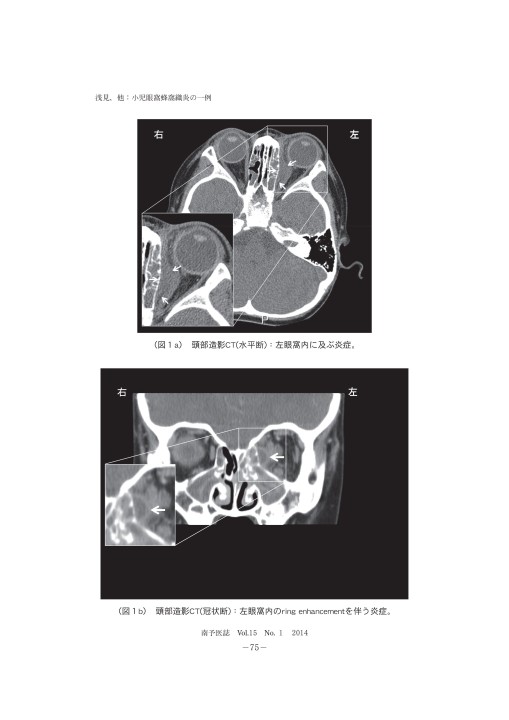

72巻2号 (18年2月) 眼窩の炎症性疾患はさまざまな原因により生じるが,その緊急性や重傷度からまずは眼窩蜂巣炎などの感染性疾患を鑑別する必要がある。 また悪性リンパ腫のような腫瘍性疾患を鑑別することも重要である。 最近注目されているIgG4眼科 62巻11号 (年10月) 眼窩蜂巣炎は眼球周囲軟部組織の急性化膿性炎症であり,炎症が眼窩隔膜よりも後方に及んでいるか否かにより眼窩周囲蜂巣炎(または眼瞼蜂巣炎)と眼窩蜂巣炎に分けられる。 眼瞼腫脹,充血,結膜浮腫は両者に共通した